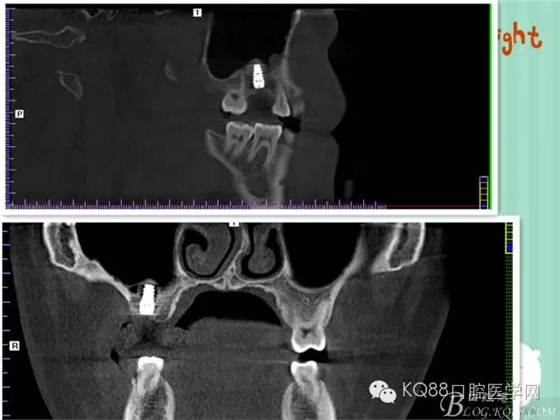

植入后,CBCT

另外一個(gè)切面。竇底粘膜完整連續(xù)。可以看到上下咬合的位置關(guān)系。

下面兩張是種植前后的對(duì)比片子。

手術(shù)前

手術(shù)后。